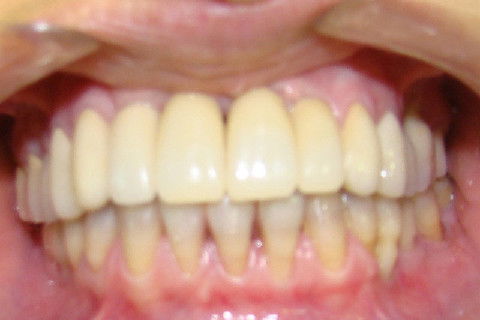

Aspecto clinico da região anterior maxilar, após remoção das proteses antigas

Finalização do tratamento reabilitador, com coroas metalo-ceramicas superiores e coroas unidas no lado direito da mandibula e unitaria da lado esquerdo

Sorriso final da paciente